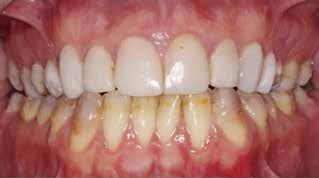

Klinisk undersøgelse viste emaljehypoplasier og hypomineralisering på 1+, +1, 2-, 1-, -1 og -2 (Fig.1). Hun havde Angle klasse II, pladsmangel i begge kæber og agenesi af -5. Der var isninger ved spisning og tandbørstning. Fundene var forenelige

Fig. 1. 40-årig sund og rask mand møder bekymret for sine slidte tænder. Klinisk ses frakturer og substanstab langs incisalkanterne på overkæbetænderne.

Fig. 1. A 40-year-old healthy man is concerned for his worn teeth. Clinically, fractures and loss of tooth substance are observed at the incisal edge of the upper front teeth.